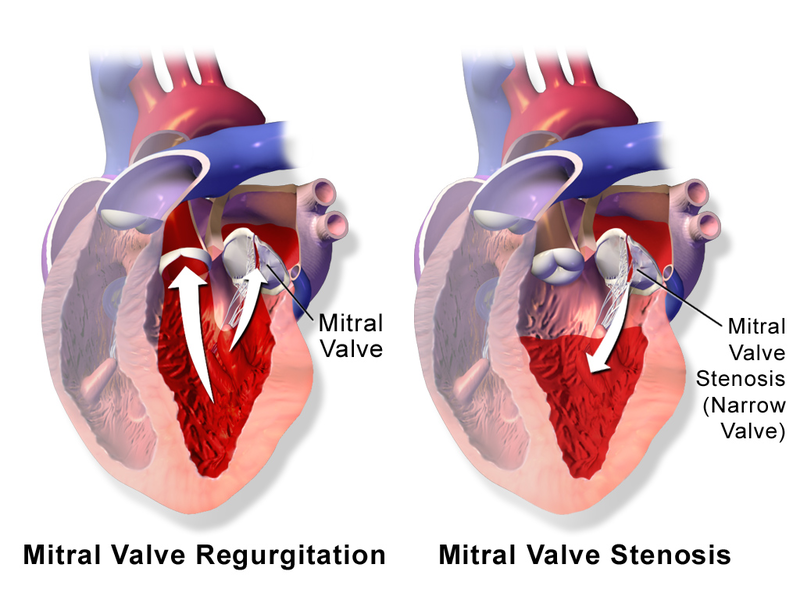

Mitral Regurgitation

Mitral regurgitation occurs when blood flows from the left ventricle into the left atrium during systole and is mainly caused by mitral valve prolapse.

Causes of mitral regurgitation include:

- Acute rheumatic heart disease

- Papillary muscle rupture following a myocardial infarction

- Left ventricle dilatation

- Infective endocarditis

Clinical features of mitral regurgitation include:

- A holosystolic blowing murmur that becomes louder with squatting due to higher systemic resistance

- Decreased left ventricular emptying

- Greater return to the left atrium on expiration

Mitral regurgitation may cause volume overload as well as left-sided cardiac failure.

Mitral Stenosis

The narrowing of the mitral valve orifice is known as mitral stenosis.

Mitral stenosis is associated with persistent rheumatic valve disease.

Clinical findings of mitral stenosis include:

- An opening snap followed by a diastolic rumbling

- Volume overload that causes the left atrium to enlarge

- Pulmonary congestion with edema and alveolar hemorrhage

- Pulmonary hypertension

- Possibly right-sided heart failure

Mitral stenosis may cause atrial fibrillation with associated risk for mural thrombi.